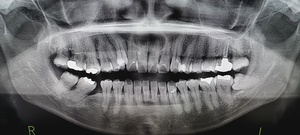

どうやって診断される?|検査・受診の流れを解説

歯科・口腔外科での診察方法

医師の視診で典型的な白斑や網目状の模様が観察されれば、口腔扁平苔癬と仮診断されることが多いです。

組織検査(生検)が必要なケースとは?

白斑が厚く、患部が硬い、出血しやすい

痛みが強く、潰瘍がある

がん化のリスクを排除したい場合

このような場合には粘膜の一部を採取する生体検査(生検)が行われます。